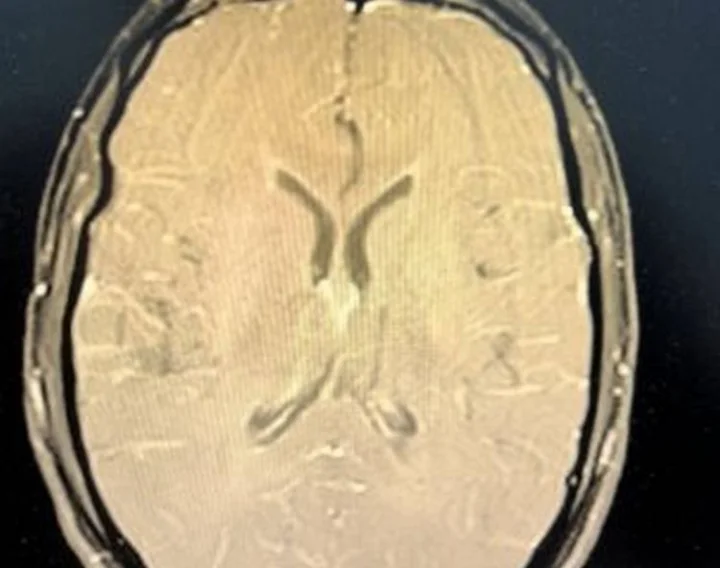

ఒక 24 ఏళ్ల యువకుడు జ్వరం, నాలుగు రోజుల నుండి కొనసాగుతున్న తీవ్రమైన తలనొప్పితో ఆసుపత్రికి వచ్చాడు. అతను విరామం లేకుండా ఉన్నాడని, అతని మెడ గట్టిగా ఉందని వైద్యులు గమనించారు, కానీ స్ట్రోక్ లేదా పక్షవాతం యొక్క స్పష్టమైన సంకేతాలు కనిపించలేదు. మెదడు ఎంఆర్ఐ, స్పైనల్ ఫ్లూయిడ్ విశ్లేషణతో సహా ప్రారంభ పరీక్షలు, మెనింజైటిస్ వైపు చూపించాయి. కానీ ఏ ఇన్ఫెక్షన్‌ను గుర్తించబడలేదు.